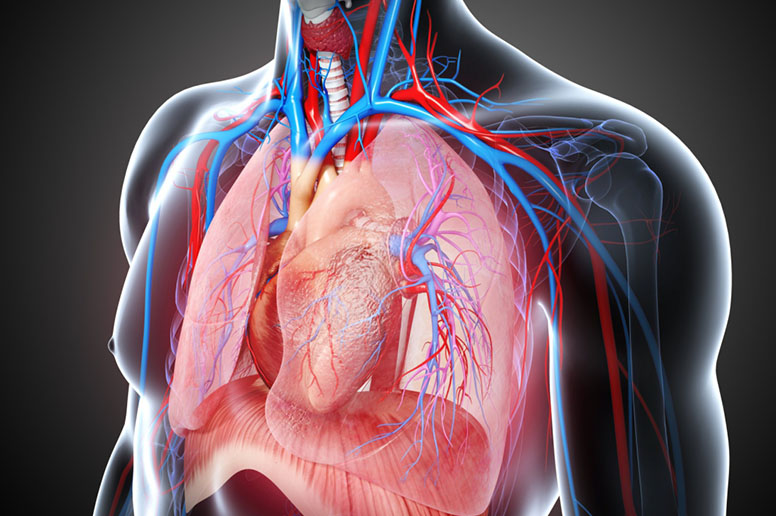

Thoracic Surgery

Thoracic surgery deals with the treatment of conditions affecting the lungs, esophagus, and chest wall. These surgeries are often necessary for patients with tumors, infections, or structural problems in the chest area. Dr. Pradeep Pokharna performs thoracic surgeries with a focus on safety, accuracy, and faster recovery. From removing abnormal growths to correcting chest deformities, his care ensures that patients can breathe and live comfortably again.